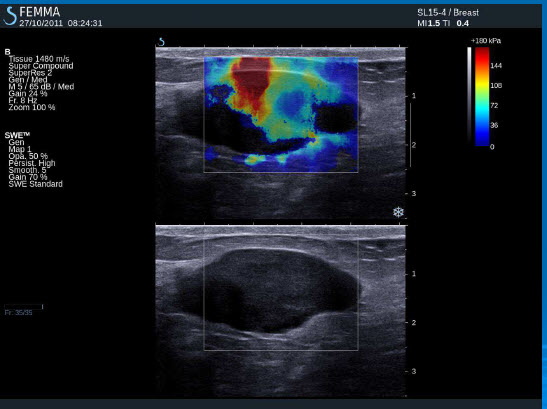

Maligní tumor (IDC)